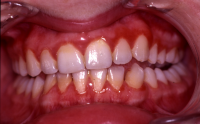

Gingivit är tandköttsinflammation som visar sig genom marginal blödning vid sondering, men där tanden ej har någon förlust av käkbensfäste.

Diagnosen gingivit används vid tänder med marginal inflammation och blödande tandkött, men ingen förekomst av marginal benförlust. Fickdjup 1–3 mm, pseudofickor kan förekomma upp till 5 mm.

Ödematös, rodnad och blödande gingiva.